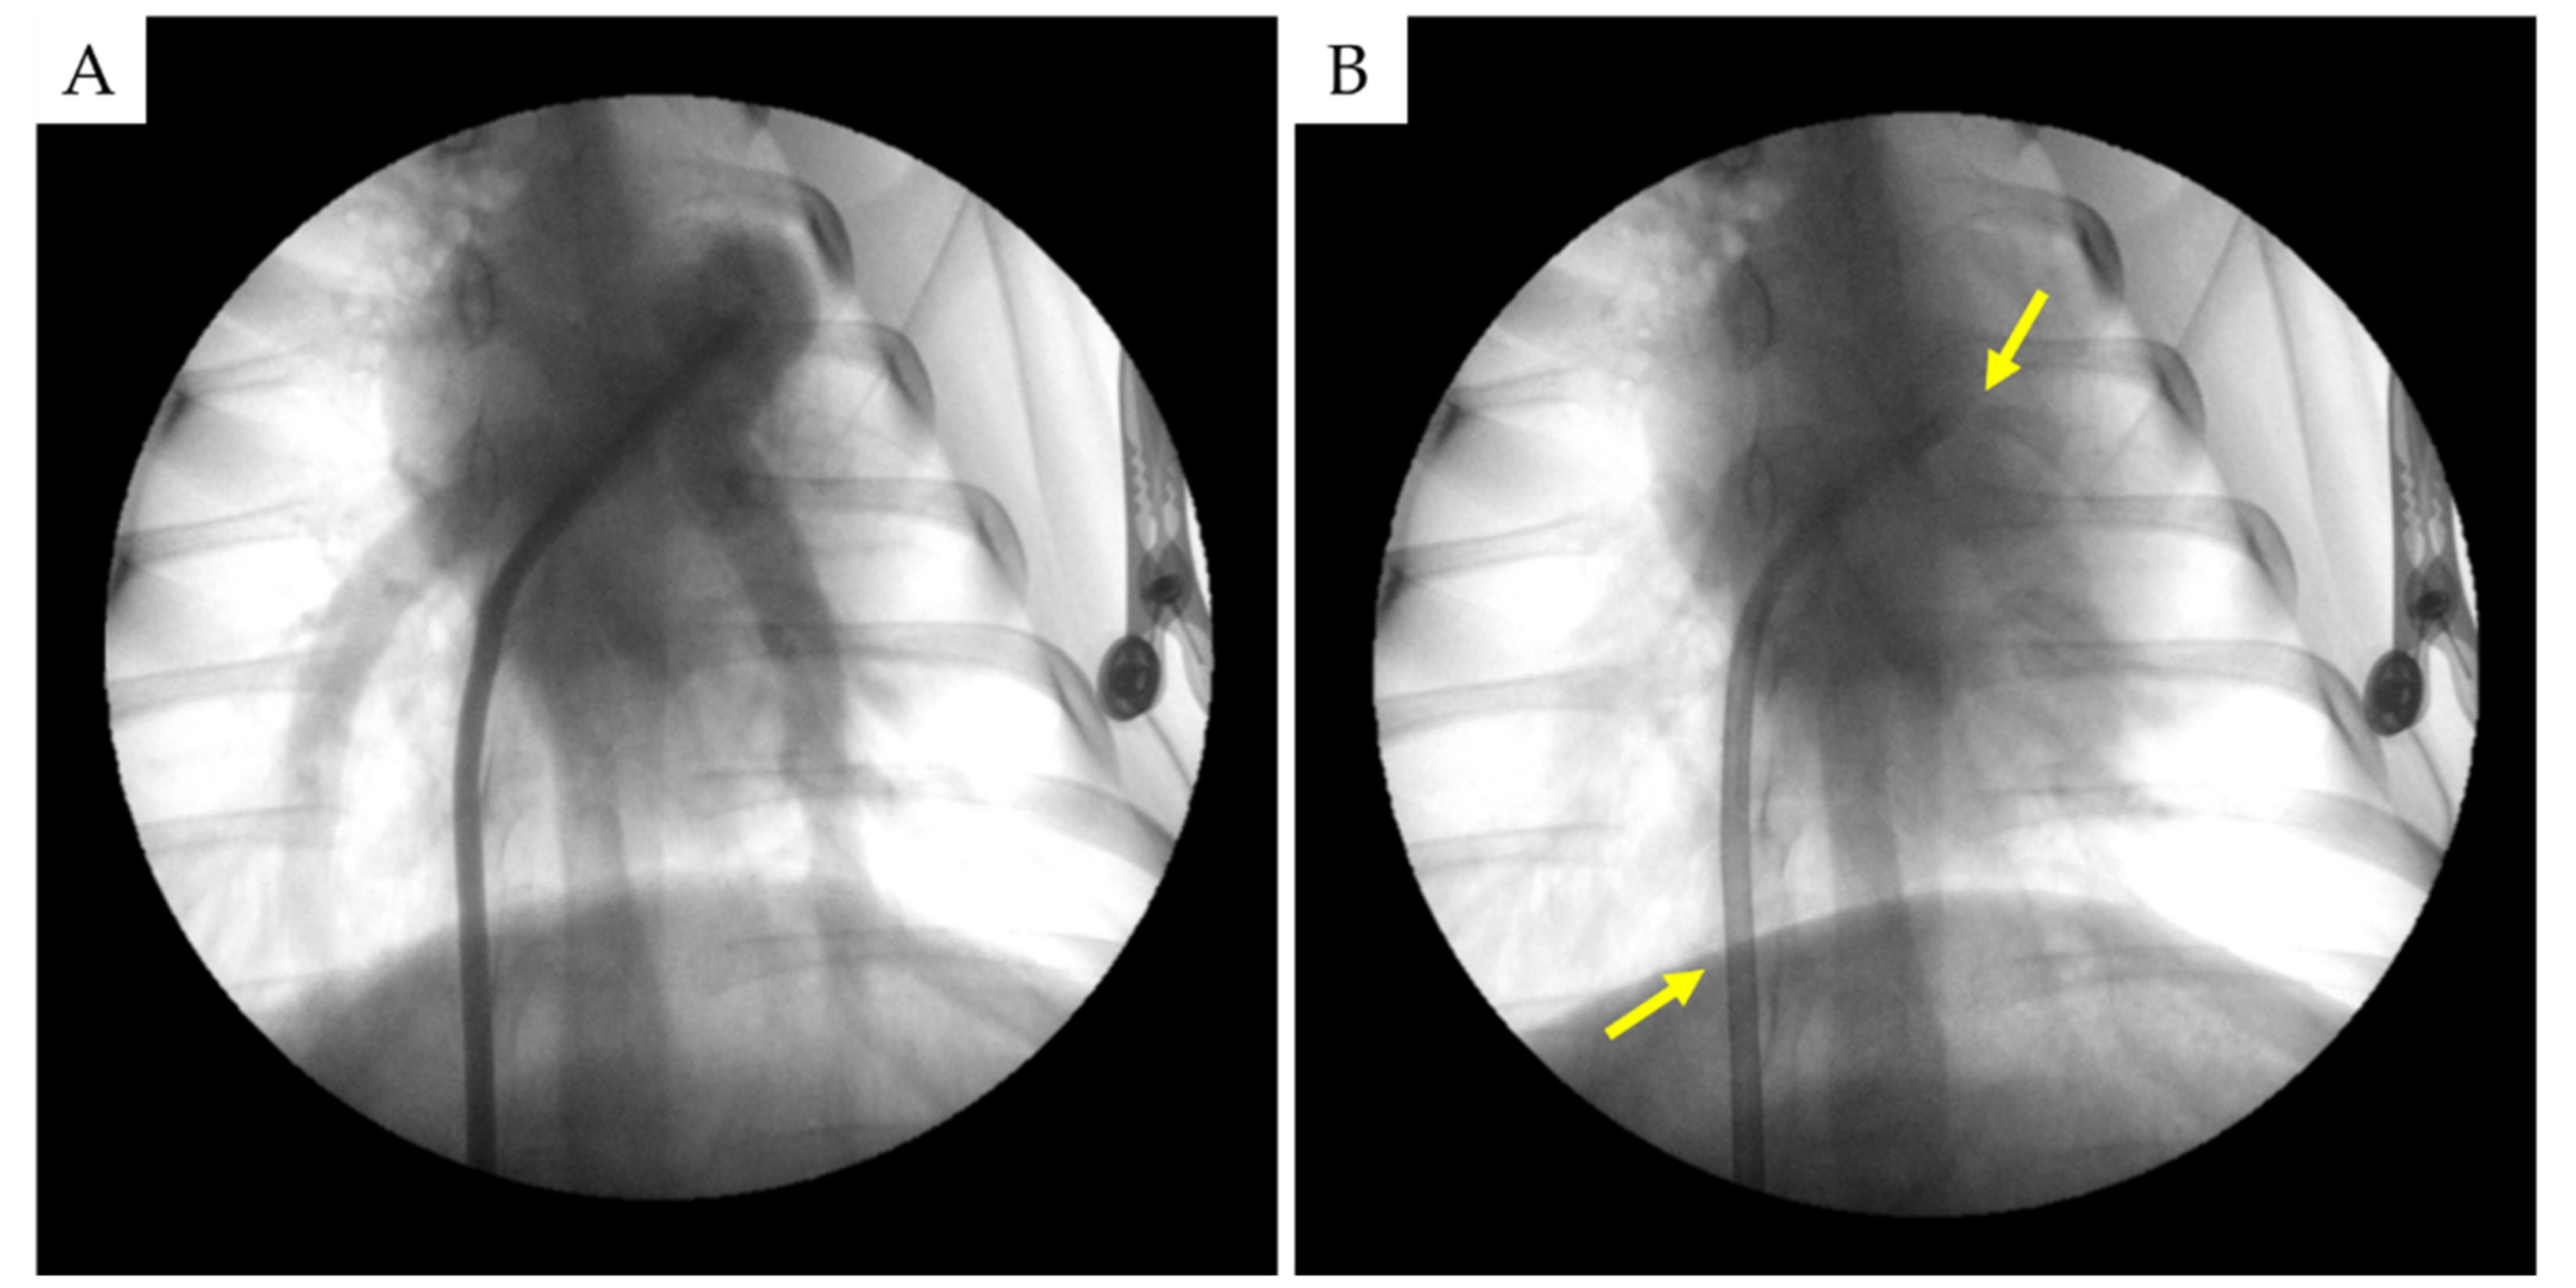

2.2. Ovine Pulmonary Artery Laser Denervation and Lesion Histological Evaluation

2.2.1. Necropsy Findings